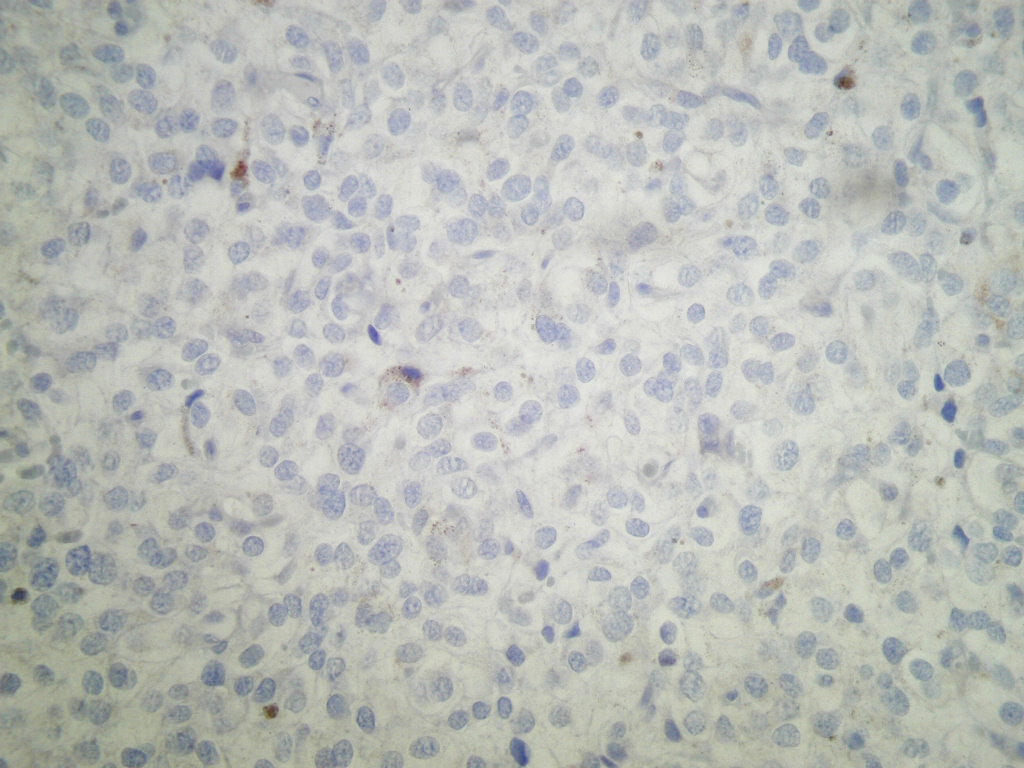

Microscopic (histologic) description

- Typical morphology: epithelioid cells with abundant, eosinophilic / amphophilic, granular cytoplasm and round / ovoid, vesicular / salt and pepper nuclei, arranged in a nested / zellballen pattern and separated by fibrovascular septae with sustentacular cells (Am J Surg Pathol 2004;28:94, World J Clin Cases 2014;2:591, Endocr Pathol 2022;33:90)

Microscopic (histologic) images

Contributed by Theodorus H. van der Kwast, M.D., Ph.D., Michelle R. Downes, M.D., Debra L. Zynger, M.D. and David Cohen, M.B.B.Ch., M.D.

Positive stains

- INSM1 (diffuse), chromogranin A (variable, often diffuse), synaptophysin (variable, usually diffuse) (Endocr Pathol 2022;33:90)

- GATA3

- Sustentacular cells: S100, SOX10

- Microscopic description: This specimen shows an unencapsulated, monomorphous population of round tumor cells in a nested / zellballen pattern with delicate vascular septa and intervening extravasated red blood cells. It predominantly involves the lamina propria of the bladder but in 1 tissue piece clearly involves muscularis propria. The tumor cells have abundant amphophilic cytoplasm and vesicular chromatin with occasional small nucleoli. There is no necrosis, diffuse growth pattern or vascular space invasion identified. The mitotic count is (maximally) 1/10 high power fields. Immunohistochemistry shows the tumor cells to be positive for GATA3 with strong and diffuse expression of synaptophysin and chromogranin, as well as retention of SDHB staining. The tumor cells are negative for AE1 / AE3, HMWK and p63. The Ki67 proliferation index is < 1%. S100 shows faint nuclear and cytoplasmic staining with occasional sustentacular cells identified.